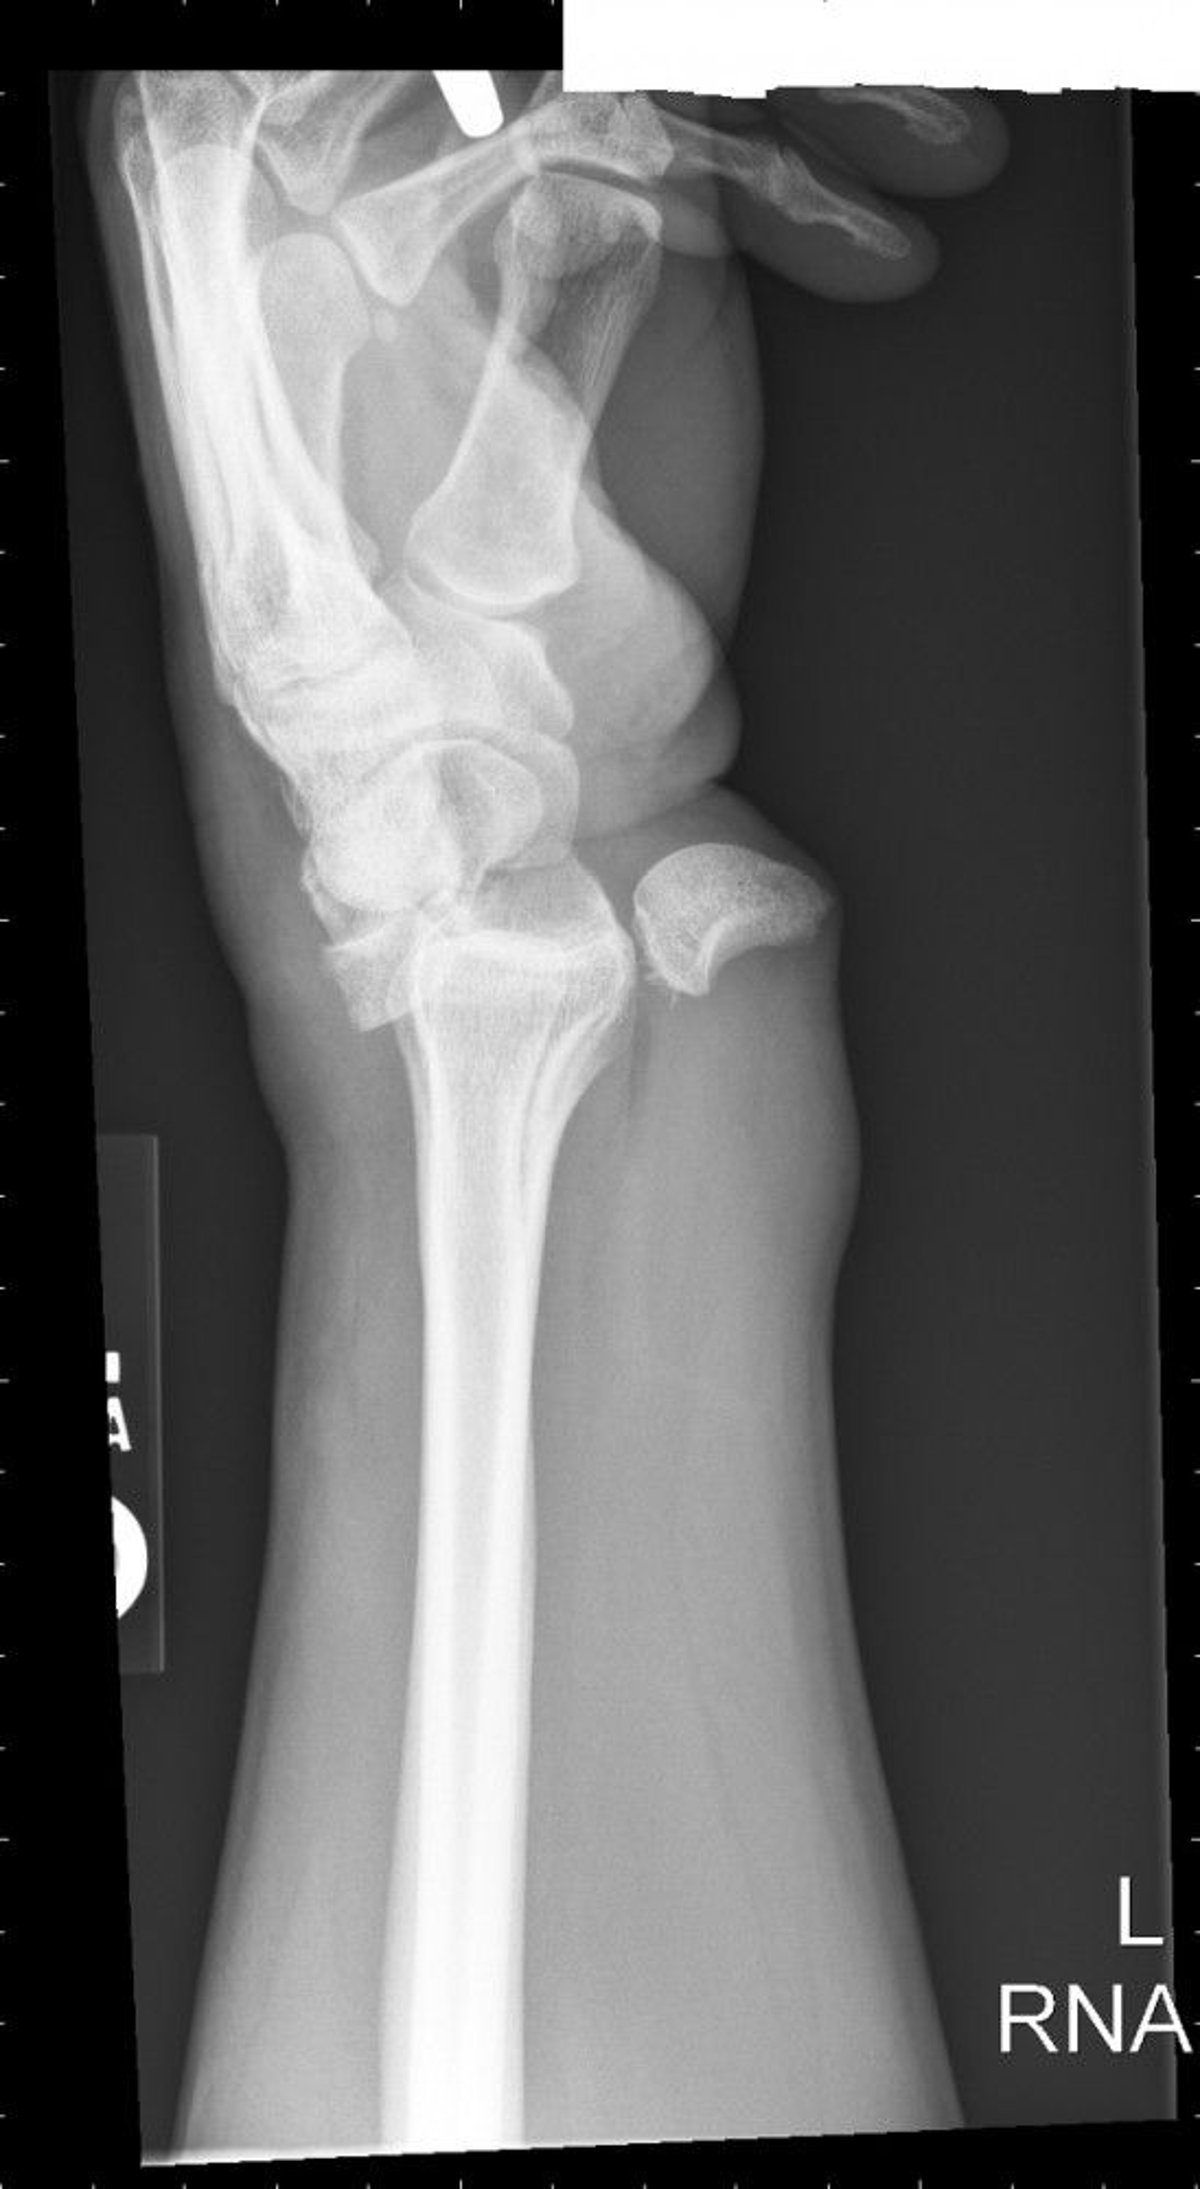

Lunate Dislocation

Lunate dislocation results in a spilled teacup configuration where the lunate is rotated and displaced volarly.

Image courtesy of Danielle Campagne, MD.